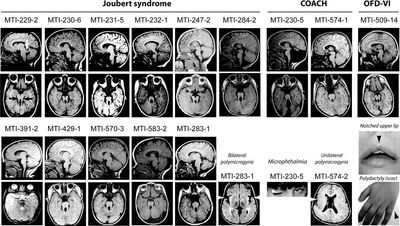

о Шесть подтипов; для каждого характерно наличие признака «моляра»:

- В научной литературе ведутся споры, касающиеся классификации заболеваний, поскольку фенотипические проявления широко варьируют

Термин «синдром Жубера и связанные расстройства» относится к пациентам с синдромом Жубера, имеющим дополнительные признаки, включая дистрофию сетчатки, заболевания почек, колобомы, затылочное энцефалоцеле, фиброз печени, полидактилию, гамартомы полости рта и другие нарушения. У значительной части пациентов с диагнозом «классический синдром Жубера» с течением времени проявляются дополнительные признаки, представляющие собой «синдром Жубера и связанные расстройства». Учитывая общность главных диагностических критериев.

Распространенность синдрома Жубер не определена. Многие авторы приводят цифры от 1:80000 до 1:100000, но эта оценка может быть занижена. Дифференциальную диагностику синдрома Жубер проводят со следующими заболеваниями: нефронофтиз, синдром Когана, врожденный амавроз Лебера, синдром Барде-Бидля, синдром Меккеля, синдром MORM (умственная отсталость, ожирение, дистрофия сетчатки, микропенис), оро-фацио-дигитальный синдром 1-го типа, гидролетальный синдром, акрокаллезный синдром.